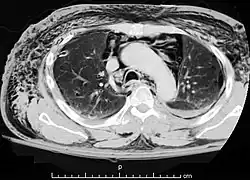

Die Diagnose eines Pneumomediastinums wird mittels Bildgebung, entweder mittels konventioneller Röntgenaufnahme (Röntgen-Thorax) oder mittels Computertomographie des Brustkorbs, gestellt. Die Computertomographie ist sensitiver als das konventionelle Röntgen. Neben dem Nachweis auch kleinster Luftansammlungen im Mediastinum liefert die Computertomographie auch Hinweise auf die mögliche Ursachen (Ätiologie).